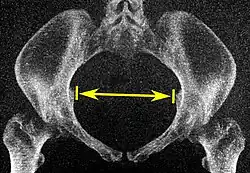

| Intertuberous diameter |

![]() Axial plane |

The closest bony points of the ischial tuberosities | 10 to 12 cm.[6] | |